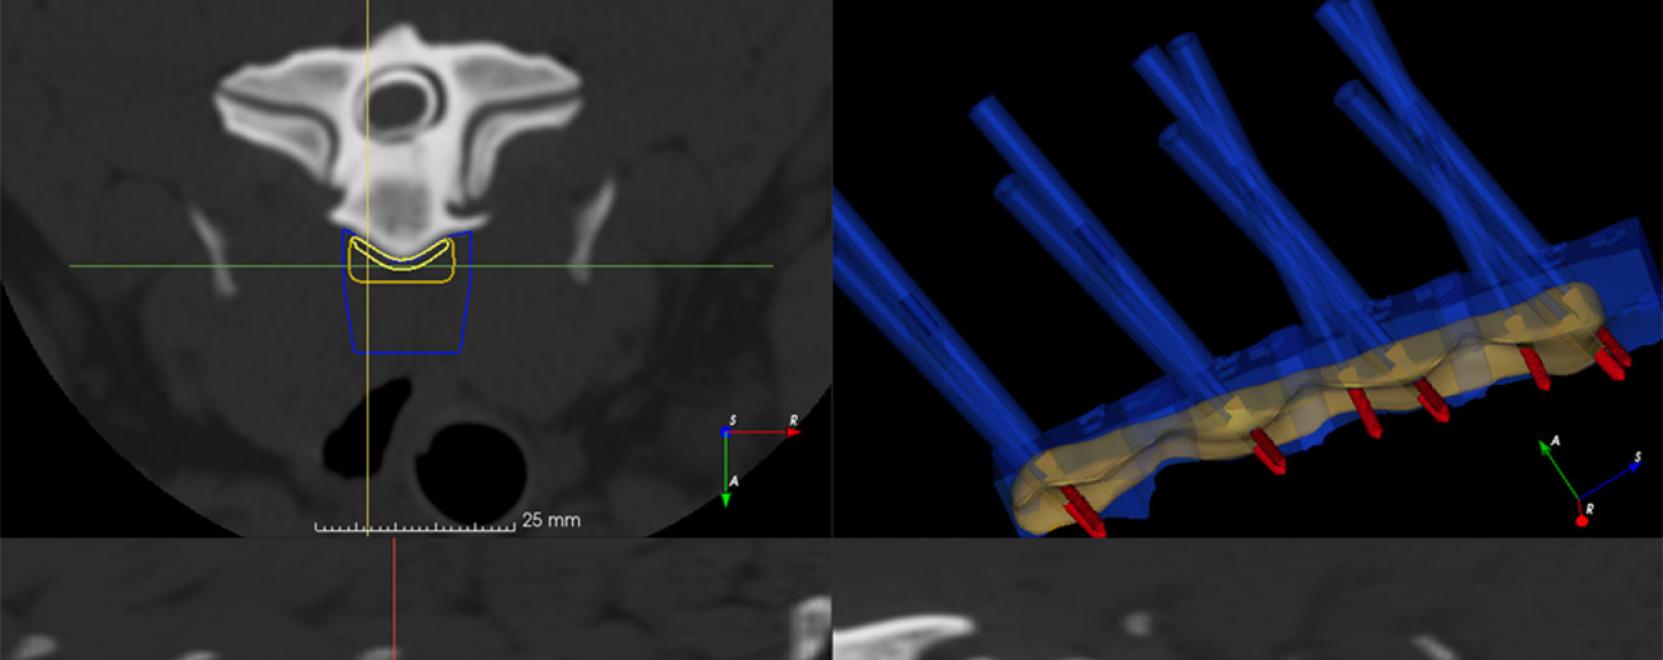

A személyre szabott orvoslás meghonosítása az állatorvoslásban is elkezdődött, melyet a Limes Model szakemberei napjaink egyik legdinamikusabban fejlődő technológiájára, a 3D-s tervezésre és -nyomtatásra alapoztak. A technológiai és az állatorvosi tudás ötvözésével a sebészek kifejezetten az adott állatra tervezett eszközökkel végezhetnek műtéteket. A szakemberek a többi között terveztek már kutya gerincműtétéhez a csigolyákhoz egyedi módon illeszkedő fúrósablonokat és rögzítőlemezt, illetve egy koponyaműtéthez szükséges implantátumot is.

„Ez több szakaszra különíthető el: az első fázisban a különböző képalkotó eljárások (mint például a CT és MRI) által készített felvételekből elkészítjük az érintett csont, testrész vagy elváltozás háromdimenziós modelljét. Mivel megfelelő programokkal ez a modell egy számítógépen interaktívan bemutatható, így már ez is sok információval szolgál a műtétet végző orvosnak. A következő szakaszban az anatómiai modellekre tervezzük rá a megfelelő implantátumot vagy a célzást segítő eszközöket, majd ezeket 3D-nyomtatással vagy pedig CNC-technológiával gyártjuk le. Így szemben a hagyományos módszerrel – amikor általában szabványmodellekből választják ki az implantátumot, és azt alakítják a műtét során az adott állat anatómiájához –, a digitális tervezéssel már eleve figyelembe tudjuk venni az egyedi sajátosságokat” – tette hozzá a szakember.

A 3D nyomtatással készülő fúró- és vágósablonoknak elsődlegesen a gerinc- és koponyasebészetben van nagy jelentősége.

Ezek segítségével biztosítható, hogy megfelelő szögben és mélységben történjen meg az előkészítő beavatkozás, így minimalizálni lehet az ezzel kapcsolatos komplikációkat is. 3D nyomtatással egyedi modellek is készíthetők az adott állatról, melyekkel az állatorvos jobban láthatja az elváltozást – bizonyos esetekben akár ki is próbálhatja rajtuk a műtétet –, illetve az állat gazdájának is szemléltetni lehet rajta, hogy milyen terápiás beavatkozásra van szükség a gyógyuláshoz.